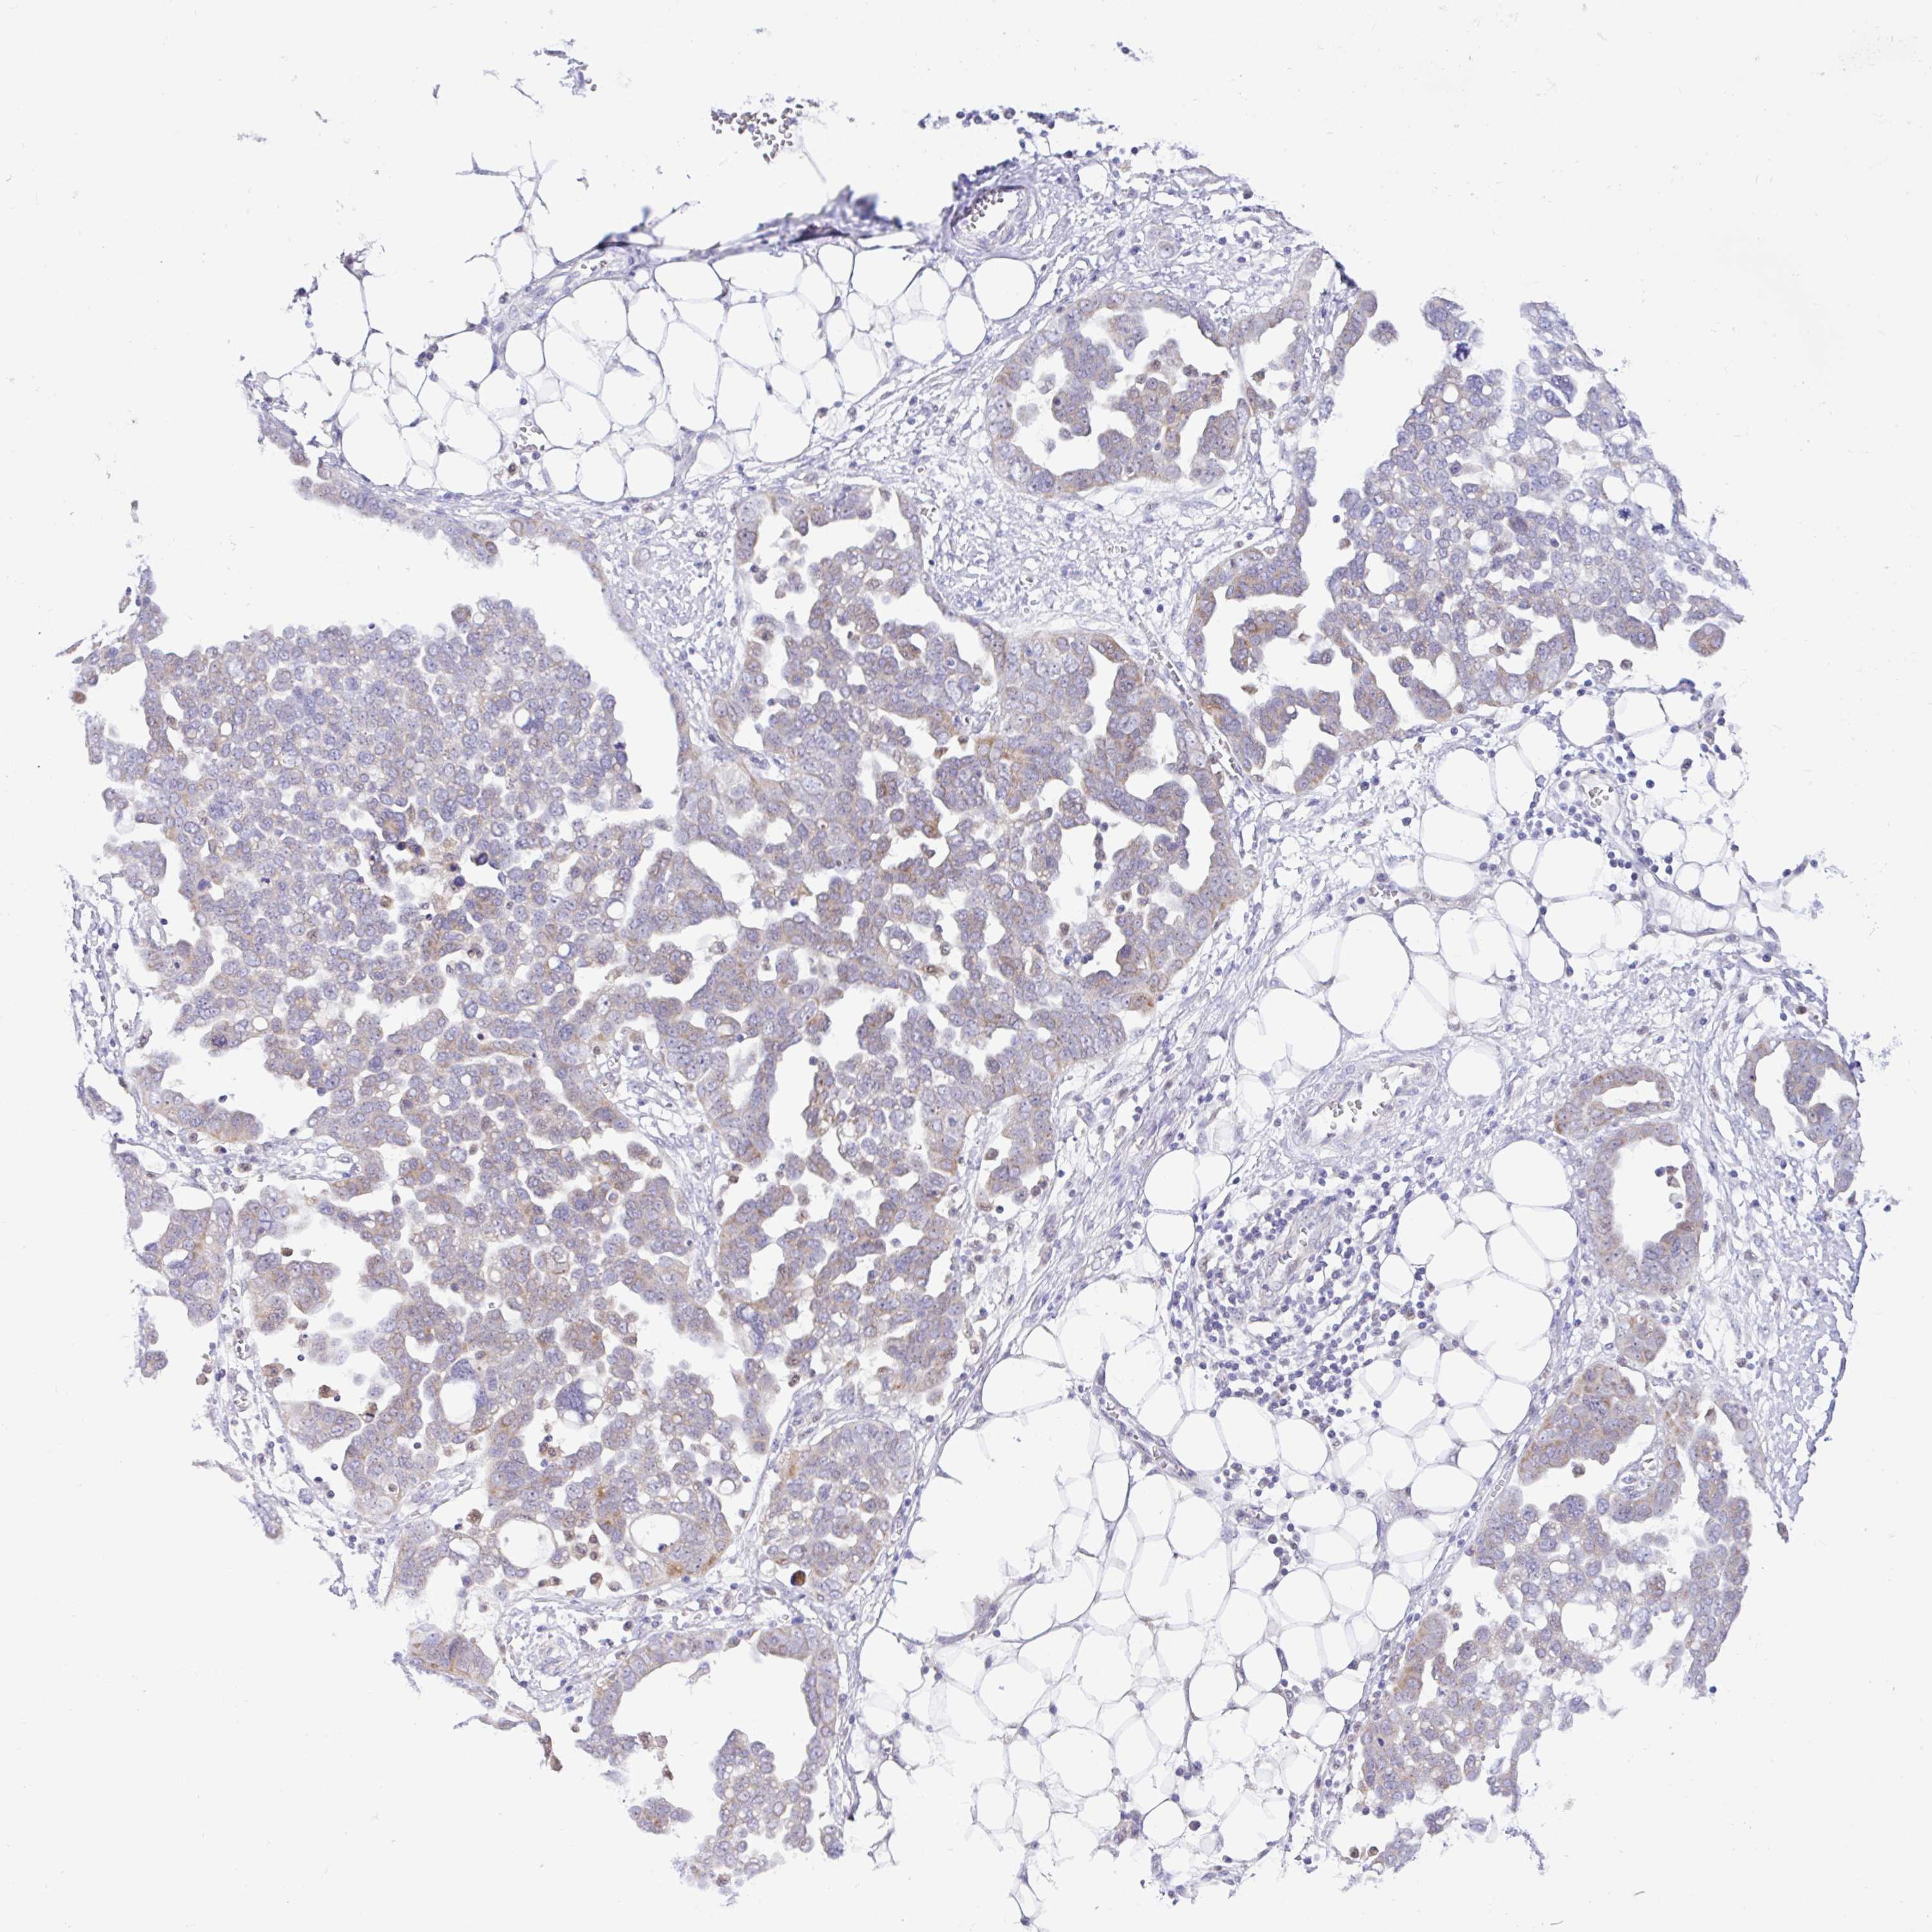

OVARIAN CANCER - Protein expressioni

A mouse-over function shows sample information and annotation data. Click on an image to view it in a full screen mode. Samples can be filtered based on level of antibody staining by selecting one or several of the following categories: high, medium, low and not detected. The assay and annotation is described here.

Note that samples used for immunohistochemistry by the Human Protein Atlas do not correspond to samples in the TCGA dataset.

Antibody stainingi

Antibody staining in the annotated cell types in the current human tissue is reported as not detected, low, medium, or high, based on conventional immunohistochemistry profiling in selected tissues. This score is based on the combination of the staining intensity and fraction of stained cells.

Each image is clickable and will lead to virtual microscopy that enables deeper exploration of all samples and also displays staining intensity scores, fraction scores and subcellular localization as well as patient and tissue information for each sample.

Antibody HPA053412

Staining

High

Medium

Low

Not detected

Intensity

Strong

Moderate

Weak

Negative

Quantity

>75%

75%-25%

<25%

None

Location

Nuclear

Cytoplasmic/membranous

Cytoplasmic/membranous,nuclear

Cystadenocarcinoma, serous, NOS

Cystadenocarcinoma, mucinous, NOS

Carcinoma, endometroid